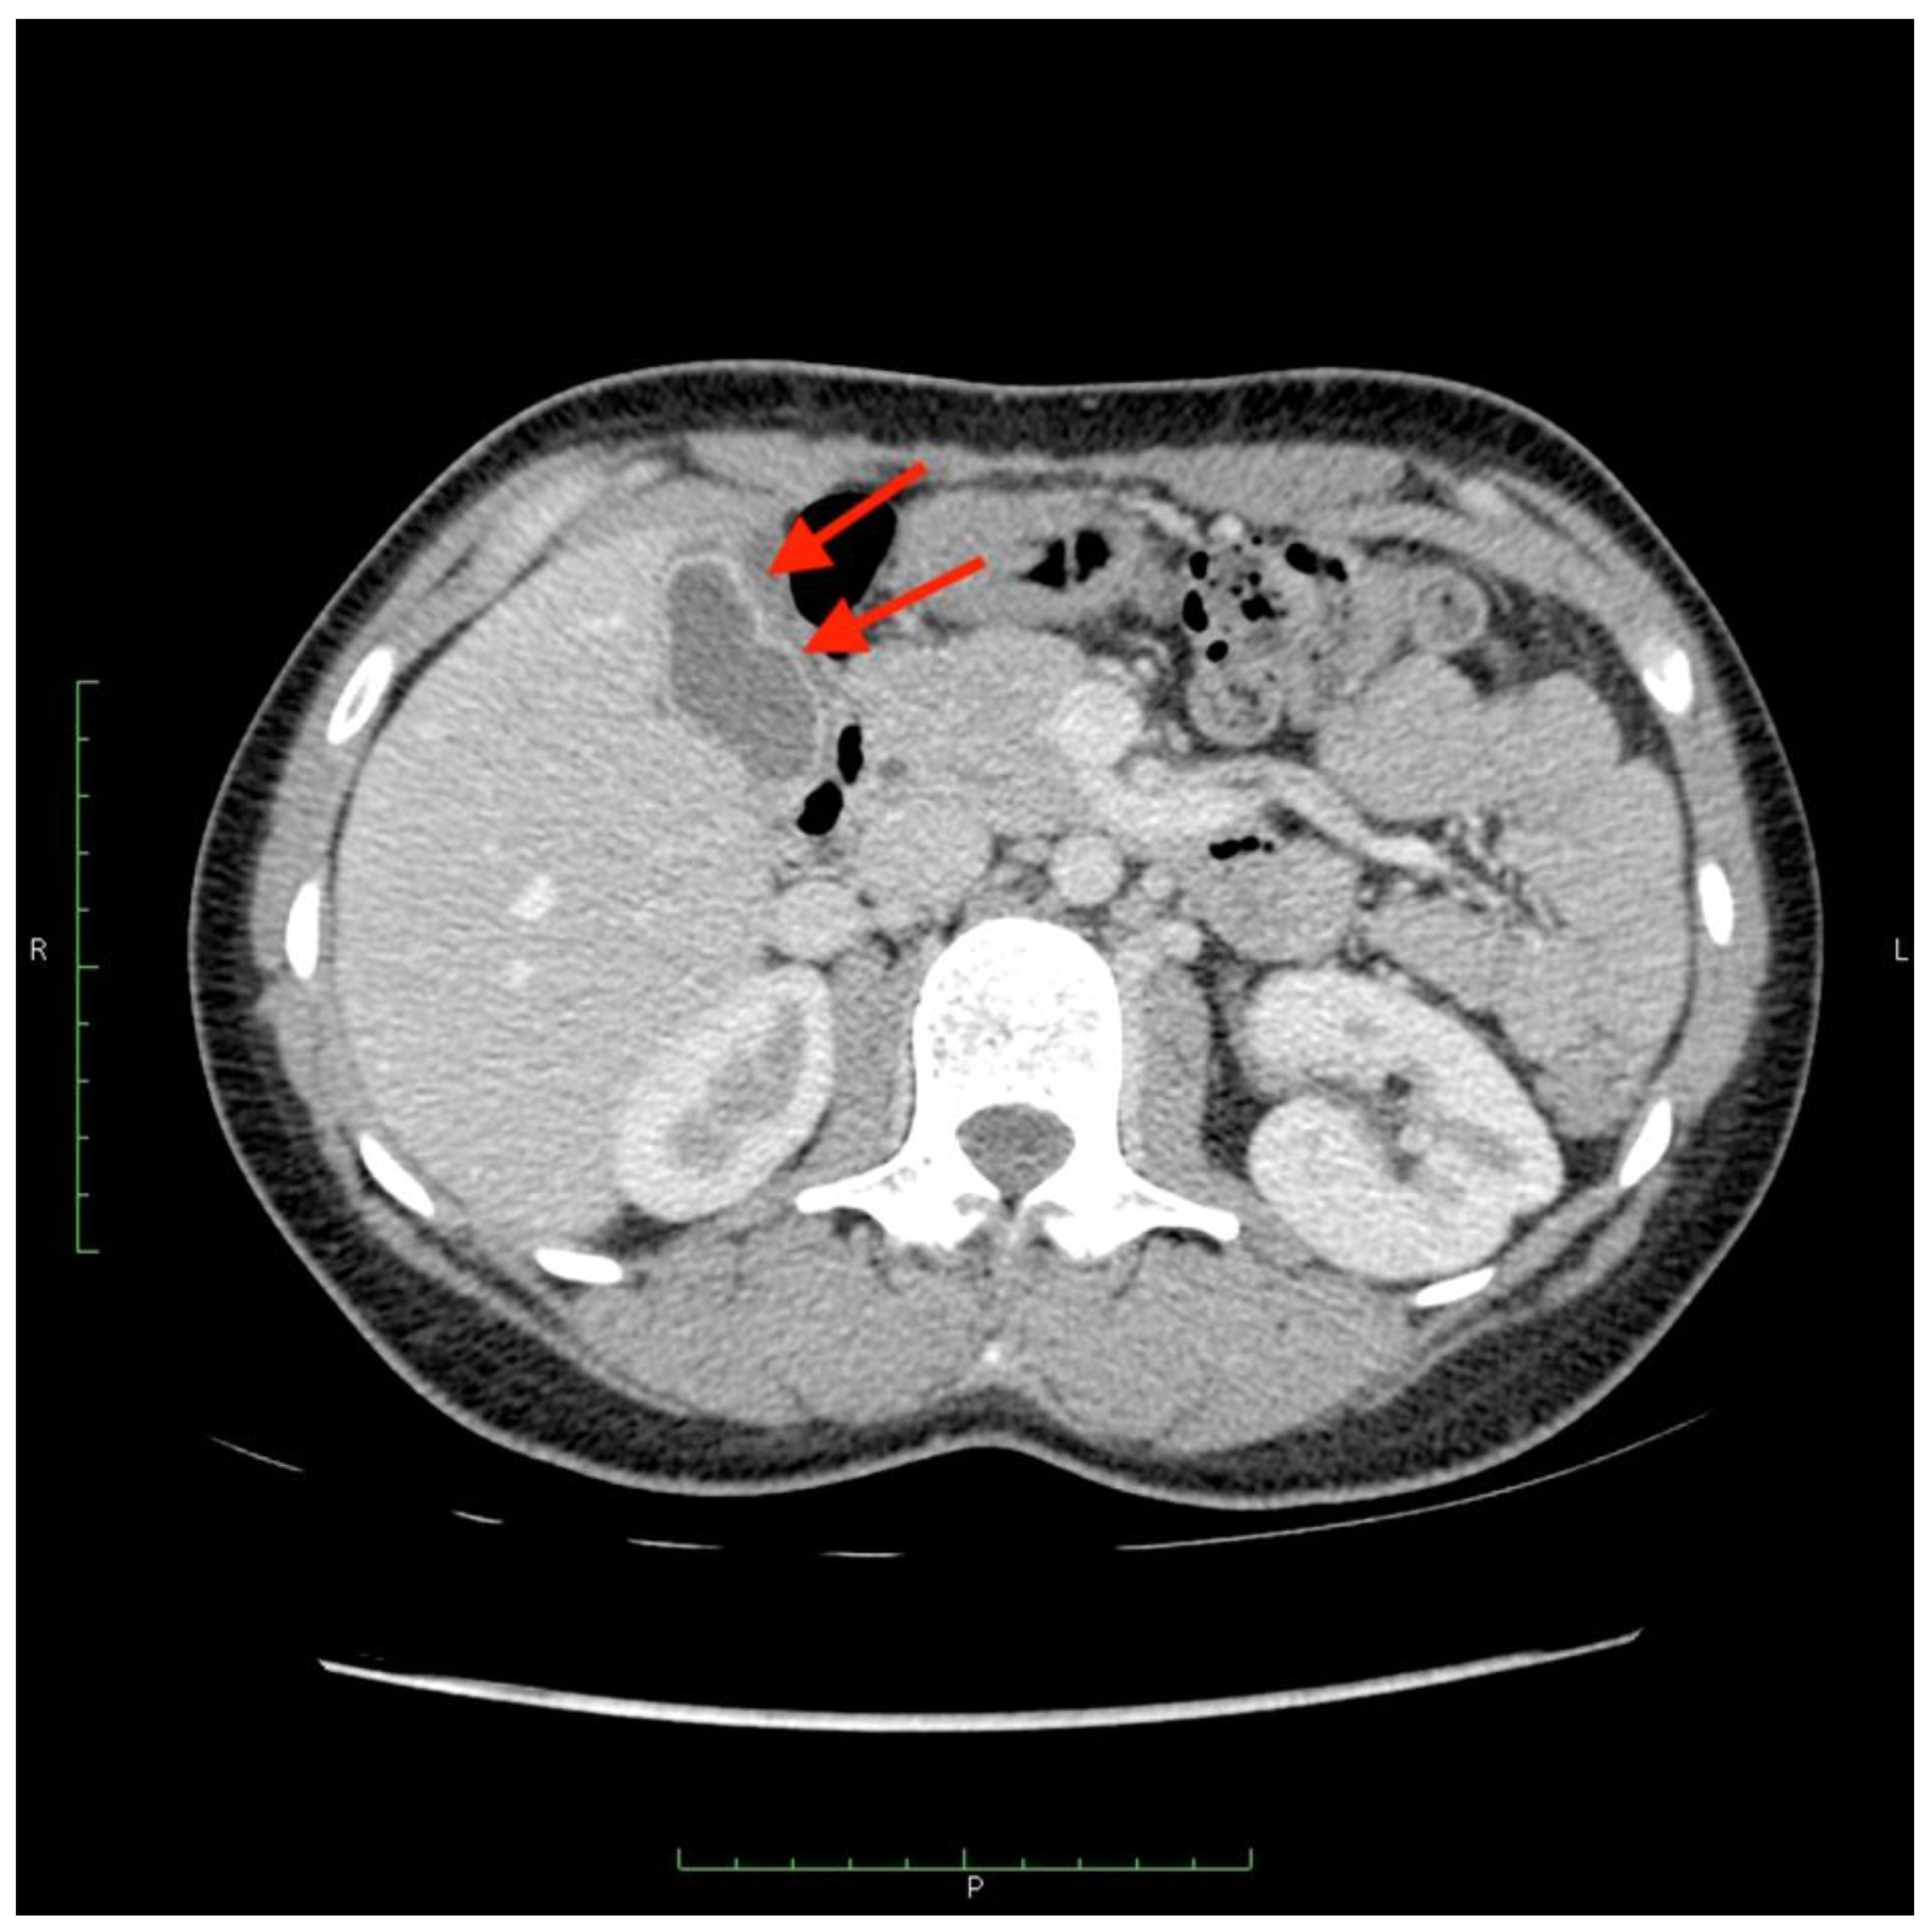

There were two leaks into the gallbladder wall after SIRT administration. Both patients had no signs of cholecystitis or a bilirubin level elevation (Figure 6 and Figure 7). No leaks were noticed in the group of five requalified patients.

Figure 7.

A computed tomography scan depicting asymptomatic cholecystitis (arrows) after the 90Y leak. The patient did not require surgery and was treated conservatively.